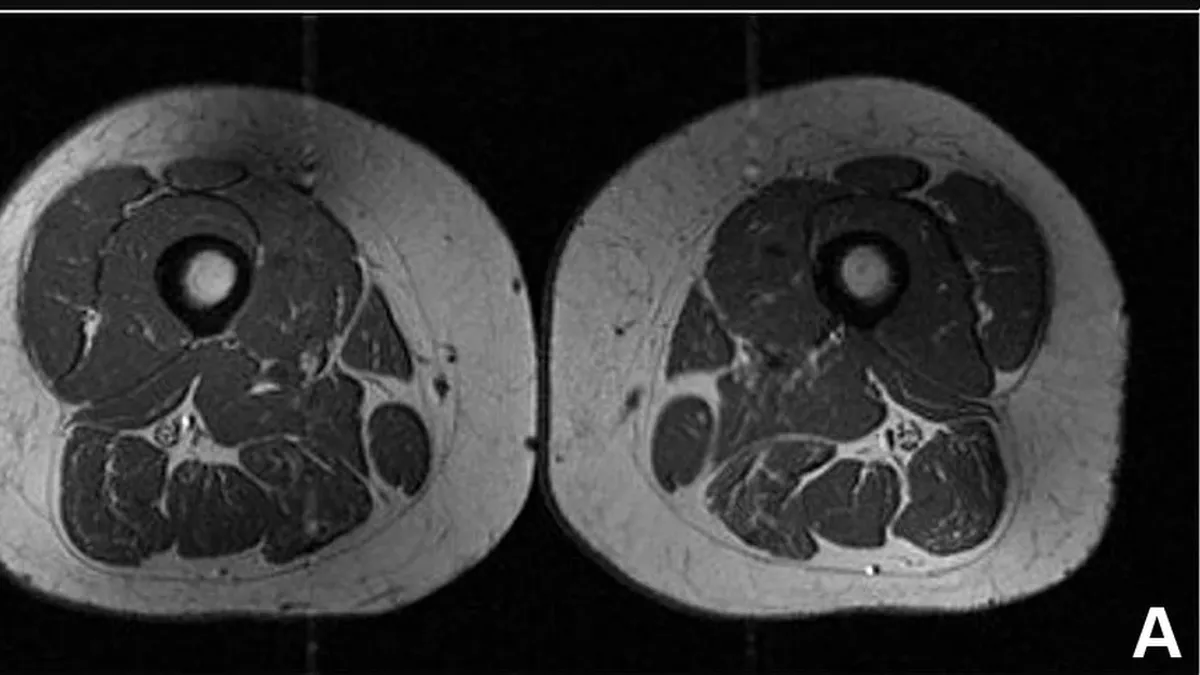

Przetworzona żywność wpływa na wygląd mięśni i tkanki tłuszczowej

Dieta bogata w wysokoprzetworzone produkty powoduje odkładanie się w mięśniach tłuszczu do tego stopnia, że ludzkie uda zaczynają wyglądać ...